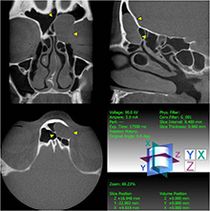

Die Diagnostik dieser Erkrankung basiert neben der Beschwerdesymptomatik (Nasenatmungsbehinderung, Schmerzen/Druck, Sekretion, Riechminderung) auf der Endoskopie der Nase und der obligaten Schnittbilddiagnostik der Nasennebenhöhlen. Hierzu verfügen wir über die derzeit modernste Diagnostik – die Digitale Volumentomographie (DVT) –, die eine hochauflösende dreidimensionale Darstellung des Geschichtsschädels, der Nasennebenhöhlen und des Oberkiefers bei im Vergleich zur konventionellen Computertomographie deutlich niedrigerer Strahlenbelastung ermöglicht.

Zyste der linken Kieferhöhle (Digitale Volumentomographie, DVT)